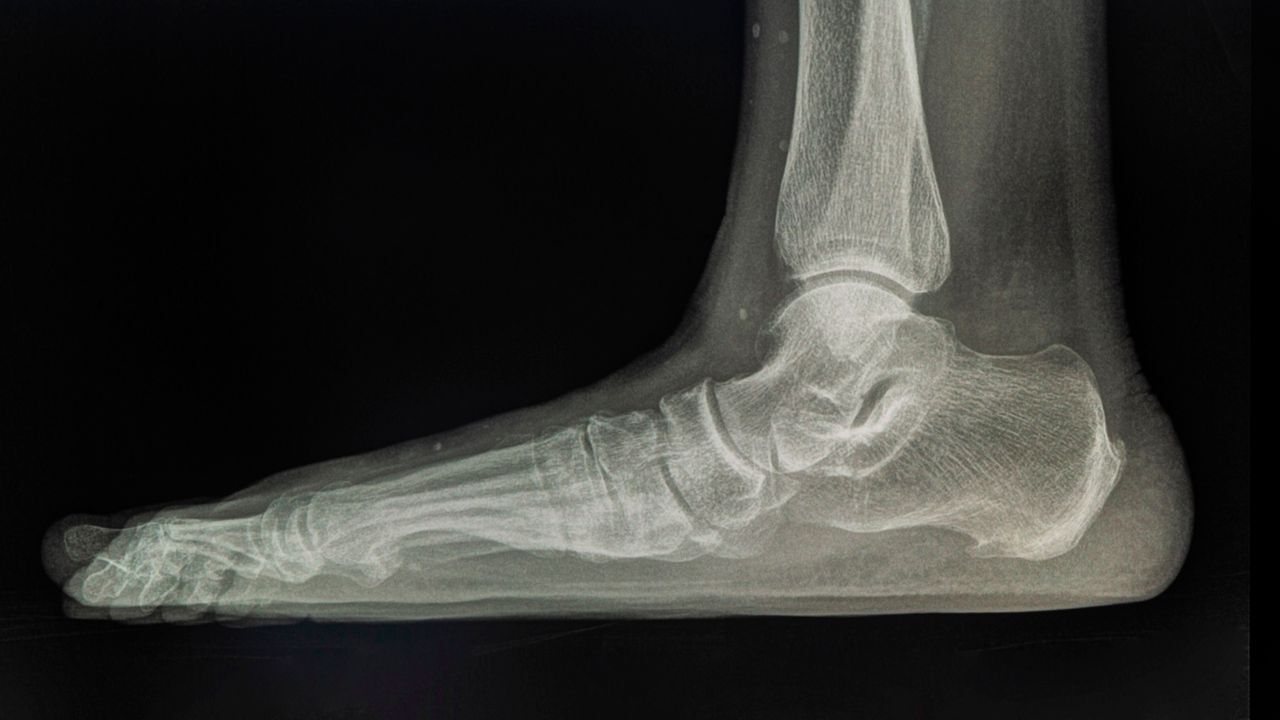

Плоскостопие — это деформация стопы. У здорового человека кости образуют два свода: продольный и поперечный. Выглядят они как арка в средней части стопы. Такая арка служит амортизатором, помогает распределять нагрузку при ходьбе.

У больного человека стопа соприкасается с полом при ходьбе. От этого страдают кости и суставы.

Свод стопы состоит из костей, связок и мышц. Когда связки и мышцы не могут нормально работать, они не поддерживают кости в правильном положении, развивается плоскостопие. Чаще всего плоскостопие начинает формироваться в детском и подростковом возрасте и со временем становится только сильнее.

Плоскостопие бывает продольным и поперечным. Но в чистом виде такое встречается редко. Чтобы узнать, есть ли у вас проблемы, нужно посмотреть на изгибы сводов стопы.

В норме отпечаток свода должен занимать одну треть линии, максимум — половину. Если отпечаток перевалил за эти значения, то пора собираться к доктору, который проведёт более точную диагностику, направит на рентгенографию и выдаст рекомендации.